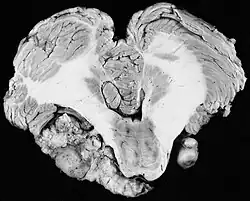

| Micrografia de um schwannoma com área Antoni A (centro e direita) e área Antoni B (esquerda). Tinção HPS. | |